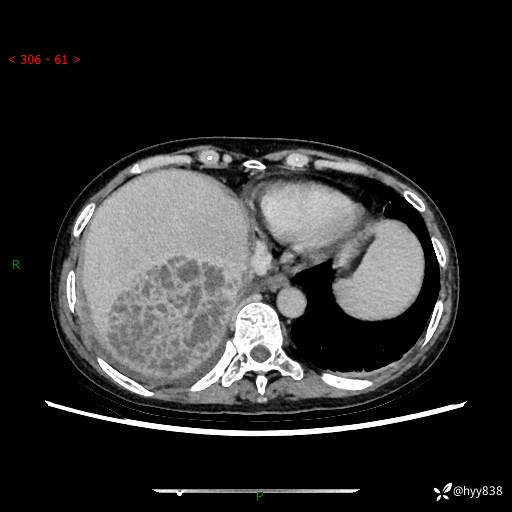

上腹部CT平扫